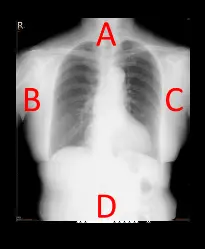

圖片為一張典型的胸部後前向(PA view)X 光影像,圖中分別標示了四個位置:

- A側:位於上胸部與下頸部區域,此處組織較薄,且肺部含有大量空氣,X 光容易穿透。

- B側與C側:為兩側外緣胸壁與腋下區域。

- D側:位於下胸部與上腹部交界處,包含橫膈膜、肝臟等實質器官以及較厚的腹部肌肉與脂肪組織,此處整體解剖厚度較厚、密度較高,X 光穿透難度較大。 在前一題中,為了獲得整體黑化度(Density)均勻的影像,需要將 X 光強度較高的陰極端放置於組織較厚的 D側,而強度較低的陽極端放置於 A側。本題則進一步詢問造成陰極與陽極兩端強度差異的物理原因。